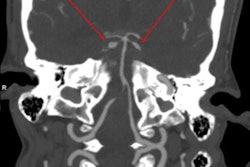

Vaginal packing

In another case, a 24-year-old woman was found to have a foreign body lodged within her vaginal cavity. On x-ray, a solitary well-defined radiopaque density was lying within the pelvis, outside of the bowel lumen. The patient required examination under anesthetic, episiotomy, suprapubic pressure, and manual delivery of a plastic cylindrical mass weighing 288 g.

X-ray of 24-year-old woman shows a solitary well-defined radiopaque density lying within the pelvis, outside of the bowel lumen.The authors have also encountered cases of colonic packing. They have seen smooth, well-defined radiopaque densities -- sometimes variable in size and shape -- scattered throughout the bowel lumen. The characteristic 'double condom' sign may be visible, and the complications can include bowel obstruction or perforation.